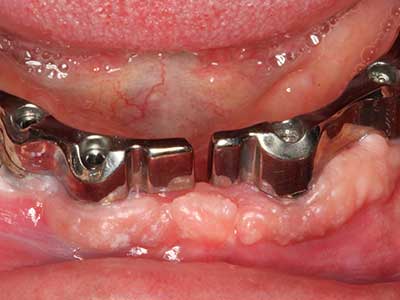

Фиг. 14: Поставяне на RSX имапланта (Bego Implant Systems, Bremen).

Фиг. 15: Прегледът на рентгеновата снимка след 1 година показва стабилно състояние на нивото на костта.

Фиг. 16: Интраоралните условия също са стабилни с поставените импланти в кератизираната гингива.